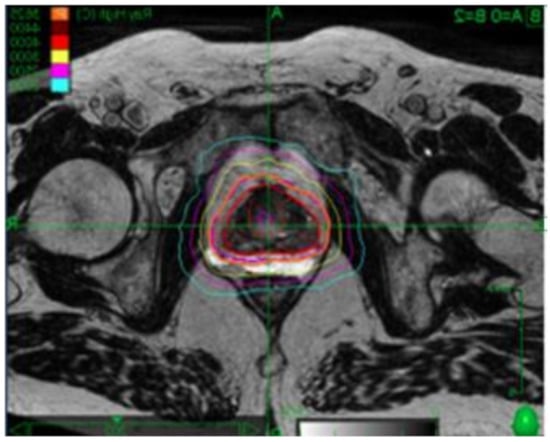

5. Contribution of Endorectal Devices in Prostate SBRT

- Dubouloz, A.; Rouzaud, M.; Tsvang, L.; Verbakel, W.; Björkqvist, M.; Linthout, N.; Lencart, J.; Pérez-Moreno, J.M.; Ozen, Z.; Escude, L.; et al. Urethra-sparing stereotactic body radiotherapy for prostate cancer: How much can the rectal wall dose be reduced with or without an endorectal balloon? Radiat. Oncol. 2018, 13, 114. [Google Scholar] [CrossRef]

- Ruggieri, R.; Naccarato, S.; Stavrev, P.; Stavreva, N.; Fersino, S.; Levra, N.G.; Mazzola, R.; Mancosu, P.; Scorsetti, M.; Alongi, F. Volumetric-modulated arc stereotactic body radiotherapy for prostate cancer: Dosimetric impact of an increased near-maximum target dose and of a rectal spacer. Br. J. Radiol. 2015, 88, 7–10. [Google Scholar] [CrossRef]

- Alongi, F.; Rigo, M.; Figlia, V.; Cuccia, F.; Giaj-Levra, N.; Nicosia, L.; Ricchetti, F.; Vitale, C.; Sicignano, G.; De Simone, A.; et al. Rectal spacer hydrogel in 1.5T MR-guided and daily adapted SBRT for prostate cancer: Dosimetric analysis and preliminary patient-reported outcomes. Br. J. Radiol. 2021, 94, 20200848. [Google Scholar] [CrossRef]